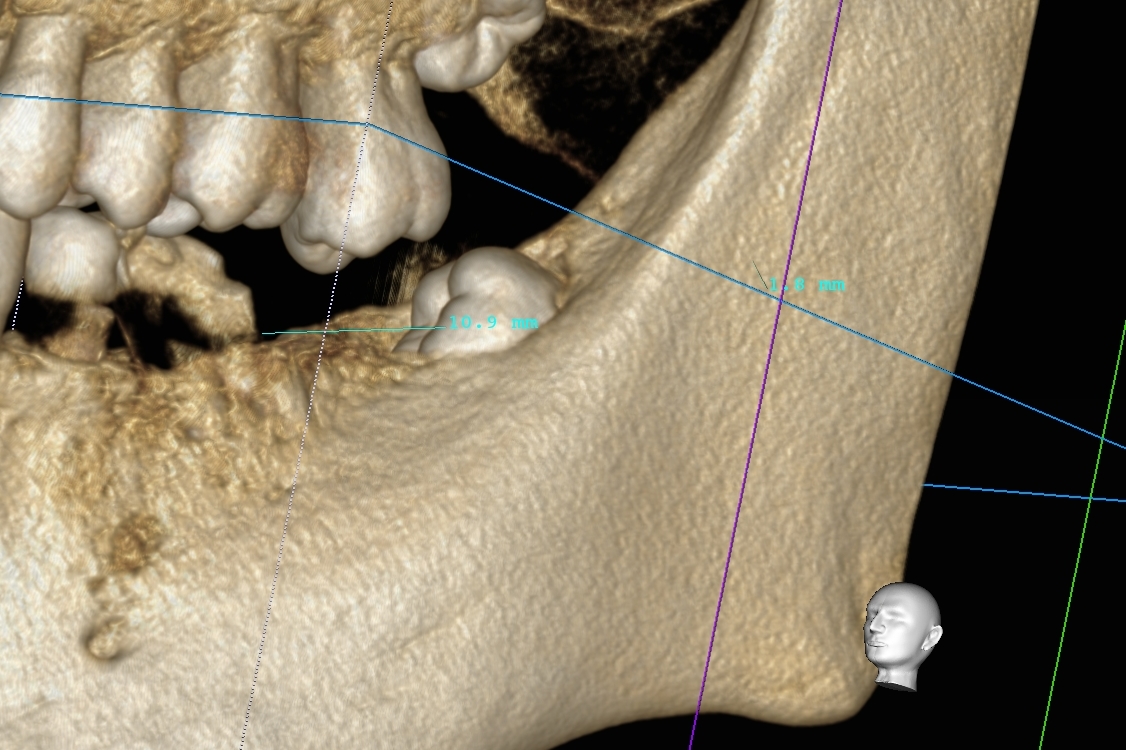

本日は親知らずを抜歯前にCT精密検査を行って抜歯したご報告です。

上記画面向かって右側下の横向きに生えた親知らずです。

以下にCT画像です。

今回はわかりやすい画像を添付致しましたが、これ以外に神経との近接がどの程度か、また根っこがどのような形をしているのかなど事前に多くの情報が得られます。